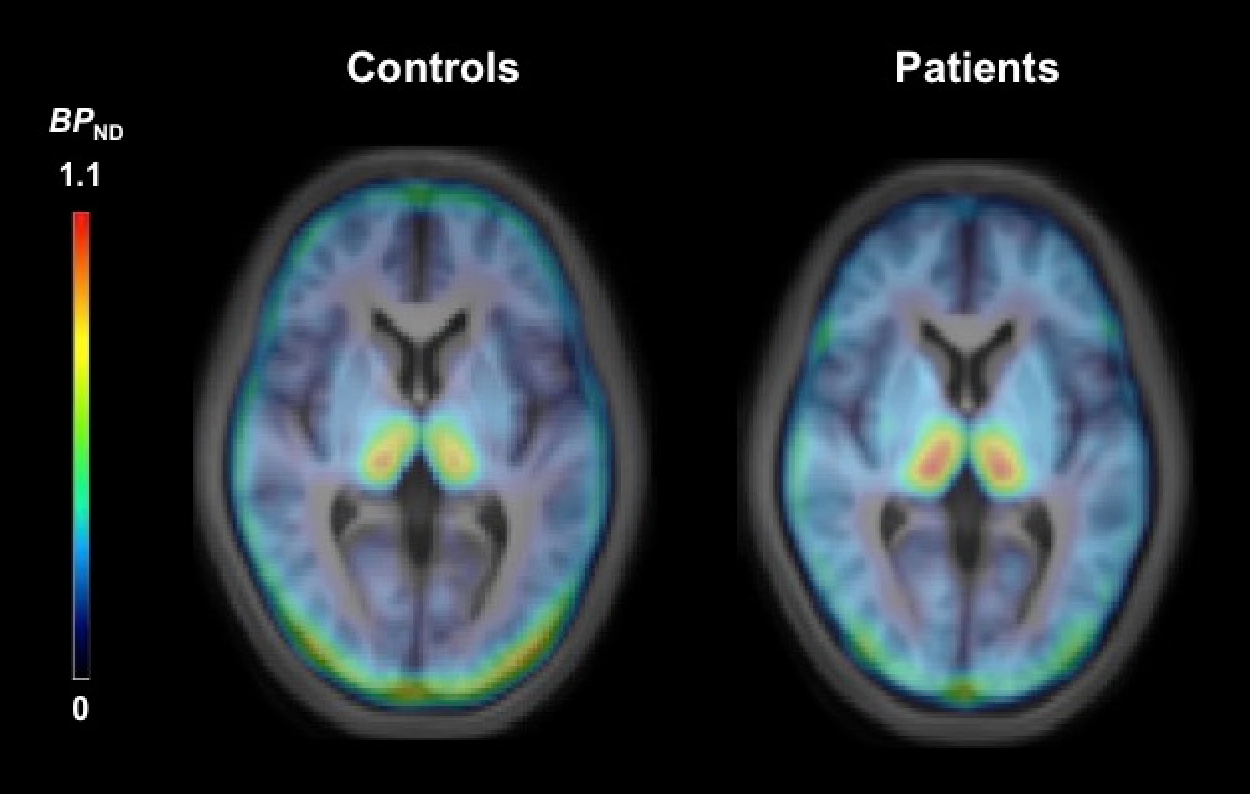

上記のように我々は最初の研究では、うつ病の患者19人と健康な人19人を比較して、脳内のNETの量をPETという画像技術で可視化しました。

NETの量は「BPND(密度のようなものです)」という値で評価され、視床(Thalamus)と青斑核(Locus coeruleus)が主な観察対象でした。この結果では、

うつ病の人では視床のNETが約29%高い。

特に前頭前野とつながる視床の領域で約28.2%高い。

NETが高いほど「注意力テスト(Trail Making Test A)」の成績が良い傾向。

これらの結果は、うつ病では視床でNETが過剰になり、ノルアドレナリンがすぐ回収されるため、集中力や意欲の低下につながる可能性を示しています。じつは脳内で直接「ノルアドレナリン」を測定する方法はありませんでした。この研究ではPETという特殊な装置を利用してうつ病と健常者のNET密度を直接測定し、NETの密度があがっている(特にうつ病直後のメランコリータイプという言われている方)ことが示されました。

ただし、これですべてのうつ病でNETが上がっているとはもちろん言い切れず、統計的には慎重な解釈が必要であり、「NETが高い=必ずうつ病」とはいえません。あくまで群としての傾向です。